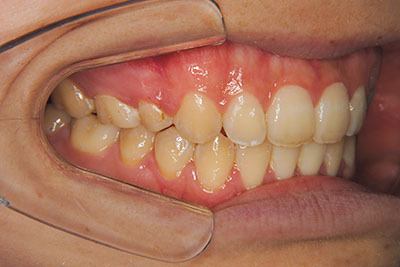

おとなの方でも矯正治療をあきらめないでください!

いくら歯が動き易くとも、本人がやる気でなければ効果は出ませんし、むし歯発生のリスクも高まります。おとなの方は顎の成長が終わっているため、治療の計画が立てやすいとも言えます。「もう大人だから…」とあきらめず、一度ご相談ください。